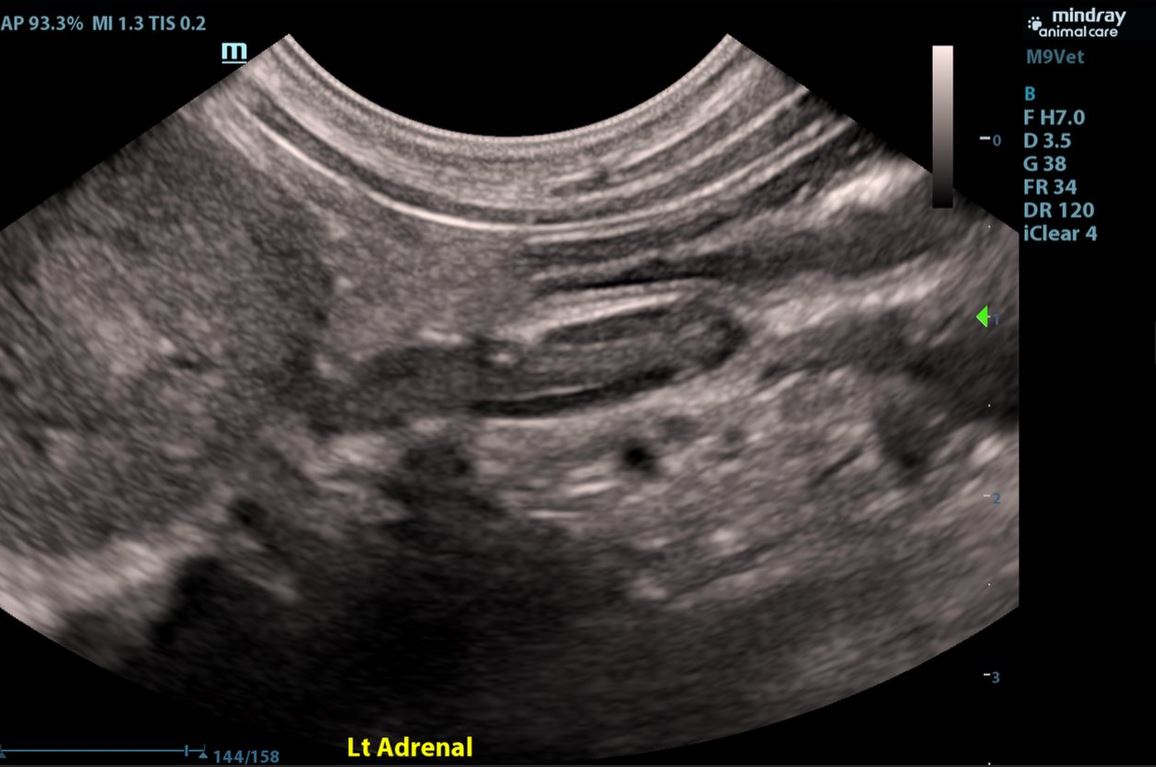

- Adrenals